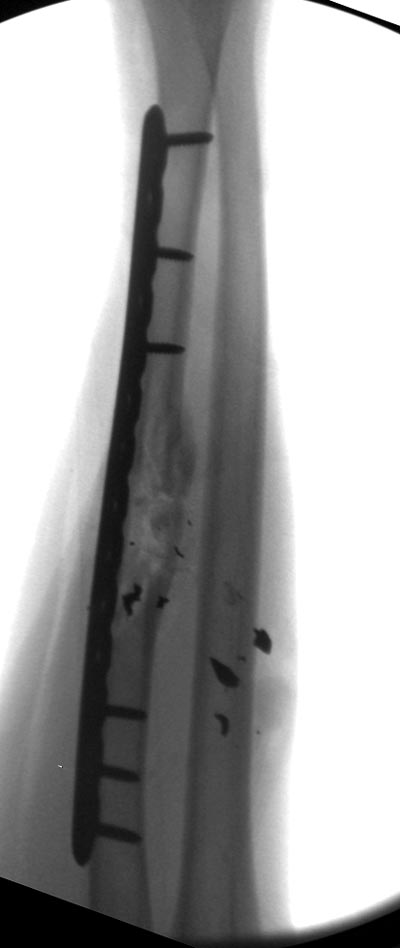

Здесь примеры: двоюродные братья с ранением предплечья, у одного

локтевая, а у второго лучевая. В следующее утро локтевая фиксирована без

обнажения фокуса травмы из небольших доступов, а второй из обычного

волярного доступа. А клинический снимок из прошлых операций...